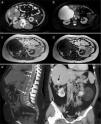

En febrero de 2012, a los 44 años de edad, sin antecedentes obstétricos de interés (ninguna historia de abortos y una gestación con hija viva y sana), fue estudiada por metrorragias abundantes secundarias a miomas uterinos y se encontraron de forma casual imágenes de angiomiolipomas renales bilaterales, un gran hemangioma hepático, pólipos rectales e islotes óseos en el esqueleto axial (fig. 1).

a). TC a la altura de los riñones donde se observa un hemangioma hepático gigante (*) y 2 angiomiolipomas renales bilaterales de baja densidad, similar a la grasa y pedículo vascular (flechas).

b). Imagen STIR axial. El hemangioma hepático es marcadamente hiperintenso y los angiomas renales muestran baja intensidad de la señal con algunas zonas hiperintensas en el izquierdo que representa la vascularización intratumoral.

c y d). Imagen eco de gradiente T1 en fase y fase opuesta. Se observa el angiomiolipoma renal izquierdo con intensidad similar a la grasa y áreas hipointensas en su interior que corresponden a las estructuras vasculares. En la imagen en fase opuesta (d) se aprecia como parte del tumor cancela su señal debido al contenido graso.

e). Reconstrucción MIP sagital de TC. Se observan imágenes redondeadas y densas en algunos cuerpos vertebrales que corresponden a islotes óseos (flechas).

f). Reconstrucción MIP coronal de TC. El hemangioma hepático ha sido resecado y en el lecho quirúrgico se aprecian los clíps tras la cirugía (flecha negra). Se evidencian con claridad los 2 angiomiolipomas renales.